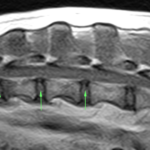

コーギー犬には椎間板ヘルニアや変性性脊髄症が起こりやすいことはよく知られています。コーギーさんが日常生活には支障はないが、ごく軽度のふらつきがあるので主治医からMRI検査を勧められ来院しました。MRIでは軽度の椎間板ヘルニアが確認されました。この程度であれば外科的手術は適応ではありません。しかし、3箇所にヘルニアがあることから同時に3箇所に処置を行うことになりました。正確に行うために外科用イメージを使いながら3部位の病変部位に経皮的に椎間板を狙ってレーザーファイバーを刺入します。このPLDDは低侵襲ではありますが、全身麻酔下で処置を行いますので、通常は翌日の退院となります。しかし、特に運動制限などは必要としていません。